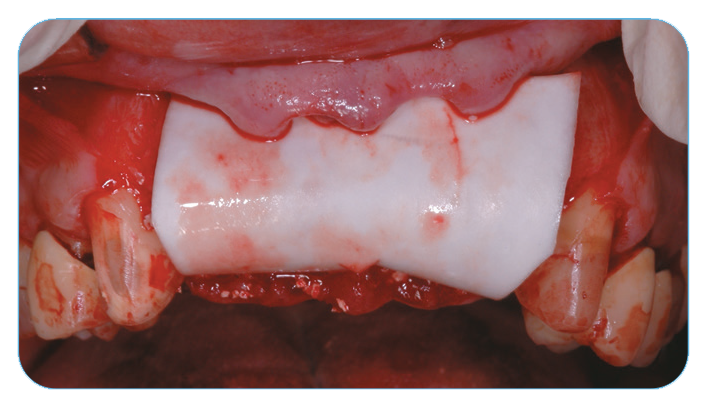

Fig. 2. Grafting with Endobon Xenograft Small Granules covered by an OsseoGuard® Resorbable Collagen Membrane.